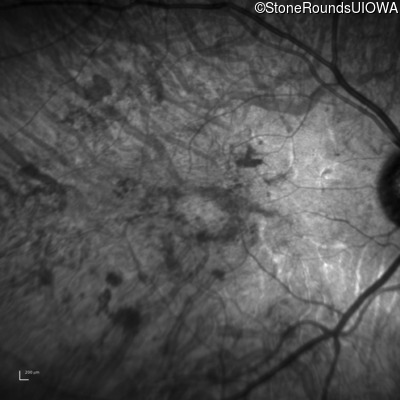

Infrared Fundus Photograph - Left - 10/300 sc

Exemplar